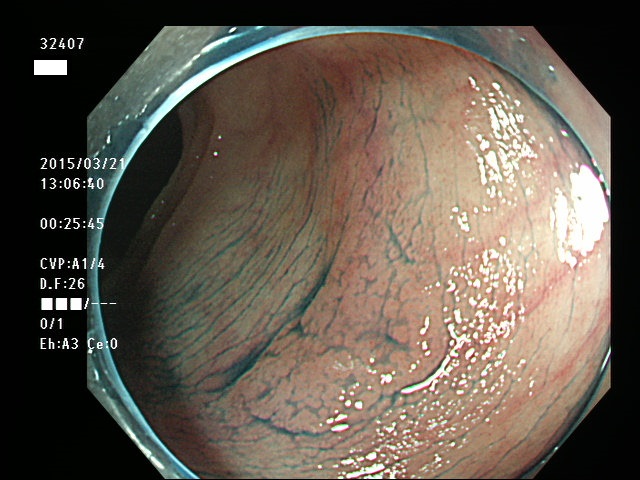

上記100名より抽出した平坦・陥凹型腺腫(=癌化の危険が高いが見落としやすい病変)の内視鏡写真

32400 32404 32405 32406 32407 32410 32411 32413 32414 32415 32416 32417